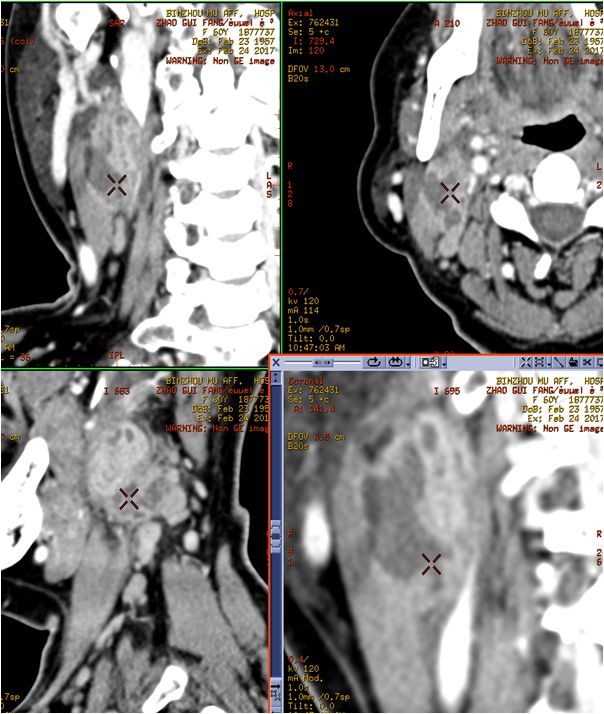

05 颌下间隙、颏下间隙

女,68岁,10天前自觉右侧下颌后牙区间断性钝痛,6天前发现右侧颌下区及颏下区肿胀,伴明显触压痛。

龋齿并冠周炎,咽旁间隙有肿大淋巴结。